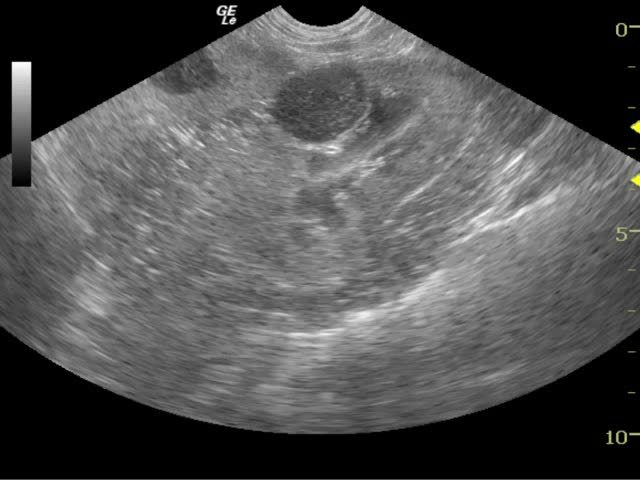

Blood work was performed several months later and revealed hyperproteinemia, hyperglobulinemia, hypercholesterolemia, hyperamylasemia, as well as elevated SAP and elevated GGT enzyme activities. Thrombocytosis was present on the CBC. The TT4 was within the normal reference range.

Recheck blood work a few months later showed an improvement of the SAP, but the ALT was elevated, and the platelet count was still elevated. The patient did not show any recurrence of the original clinical signs. Approximately one year later, she presented for signs of diarrhea and polyuria/polydipsia. The physical exam showed both nuclear sclerosis and cataracts bilaterally, discharge in the right ear, persistent DJD, as well as muscle atrophy of both hind limbs. The dog was administered subcutaneous fluids, injectable gastroprotectants, antibiotics and anti-diarrhea medications. She was discharged with oral gastroprotectants and anti-diarrheal medications.